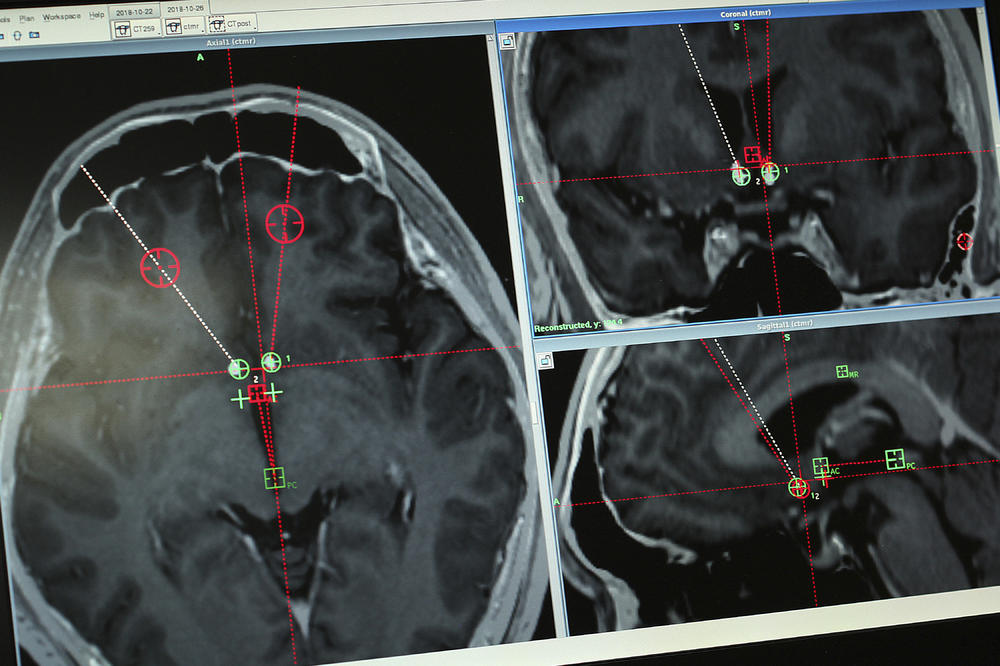

Studija objavljena ranije ove godine u Frontiers in Aging Neuroscience otkrila je da mozak može ostati aktivan tokom, a možda čak i nakon trenutka smrti.

Lekari su sprovodili kontinuiranu elektroencefalografiju (EEG) na pacijentu koji je imao epilepsiju, i to u vreme kada je pacijent imao srčani udar i umro tokom procesa. To im je omogućilo da zabeleže aktivnost ljudskog mozga tokom smrti i otkrili su ritmove aktivnosti slične vraćanju pamćenja, sanjanju, meditaciji i svesnoj percepciji.

Organizator studije dr Ajmal Zemar, neurohirurg sa Univerziteta u Luisvilu, kaže da bi to moglo značiti da je ideja da nam život ‘bleste pred očima dok umiremo’ utemeljena u nauci.